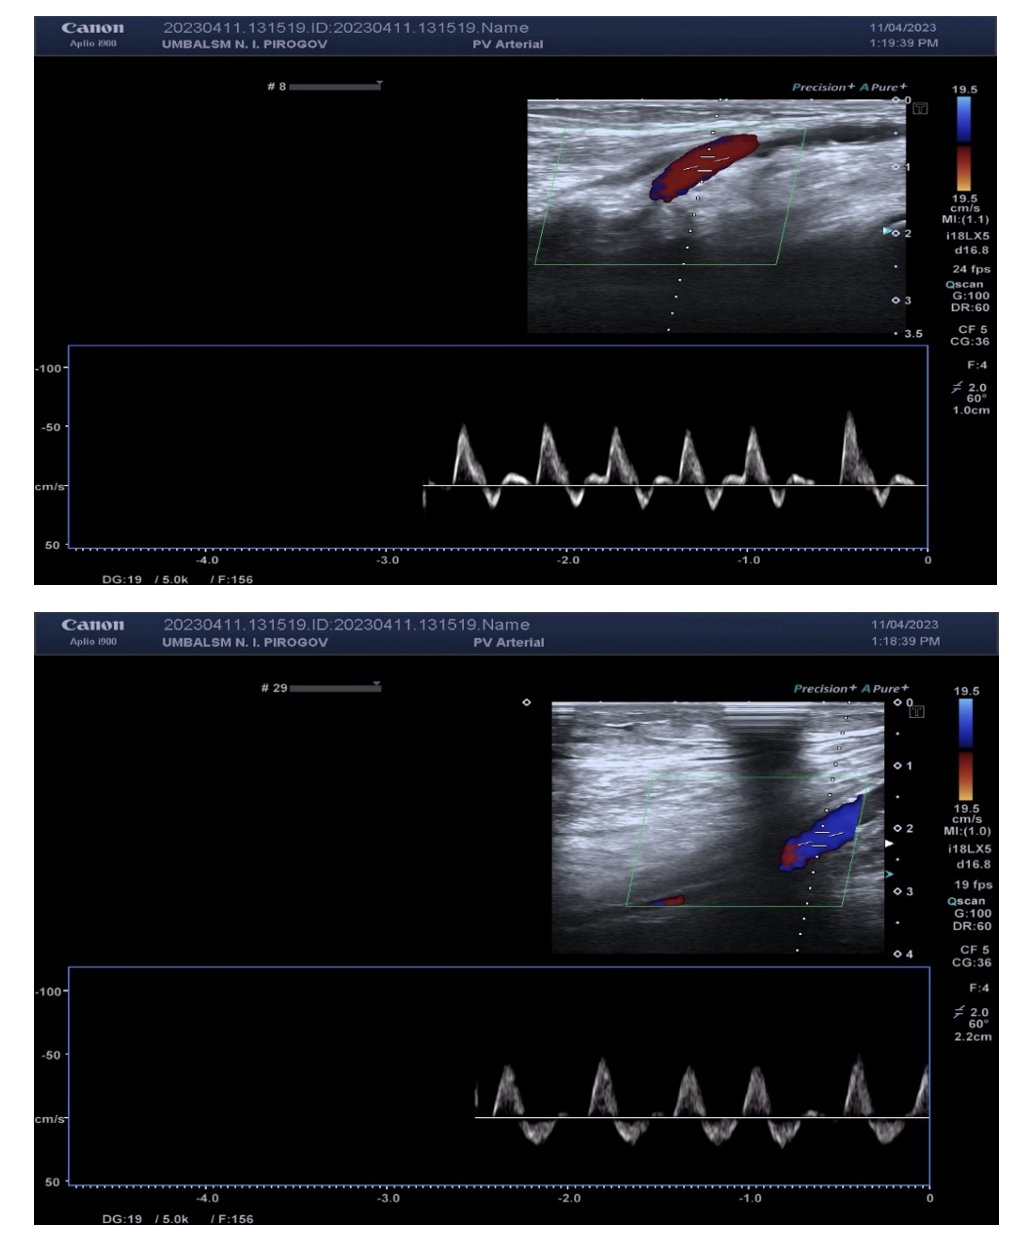

The patient was discharged after 3 days. She returned 15 and 30 days later for a planned Doppler sonography, which objectified the preserved result of the EVT of the right axillary, brachial, radial, femoral, popliteal, and posterior tibial arteries (Figures 13A-C).